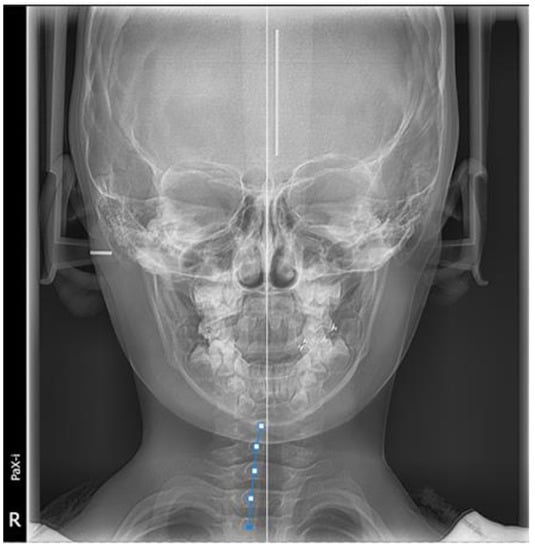

Furthermore, during orthodontic treatment, his parents visited the ENT department for the hoarseness of the boy’s vocal cords. Rhinoscopic examination revealed enlarged adenoids that blocked 1/4 of the posterior nostril and bilateral vocal fold nodules. The boy was also diagnosed with second-degree tonsillar hypertrophy, variable rhinitis and chronic sinusitis (schematic in Figure 12; the whole timeline of disease history in Figure 13). The otolaryngologist prescribed nasal drops for rhinitis and suggested a follow-up for other diseases, including tonsillar and adenoids. After treatment, the bilateral nasal mucosa swelling was alleviated, as indicated in Figure 3. Moreover, the intraoperative posteroanterior cephalograms revealed a mild flexion of the cervical spinous process, which required observation and follow-up according to a spine surgeon (Figure 14). The therapy duration was seven months, after which all the chief complaints were resolved (Figure 15 and Figure 16).

Moreover, the intraoperative posteroanterior cephalograms of the patient revealed a mild deviation in the spinal spinous process (Figure 14), which may relate to the pathogenesis of the scissor bite. A study also suggested that thoracic scoliosis was correlated with scissor bites and asymmetry in the area of the brachial band, leading to compensatory scoliosis of the cervical spine and hyper-kyphosis in the thoracic spine [30]. As the etiology of the scissor bite remained unclear, we speculated that it might serve as a cause for the malocclusion in this case.

Figure 14. Intraoperative posteroanterior cephalograms.